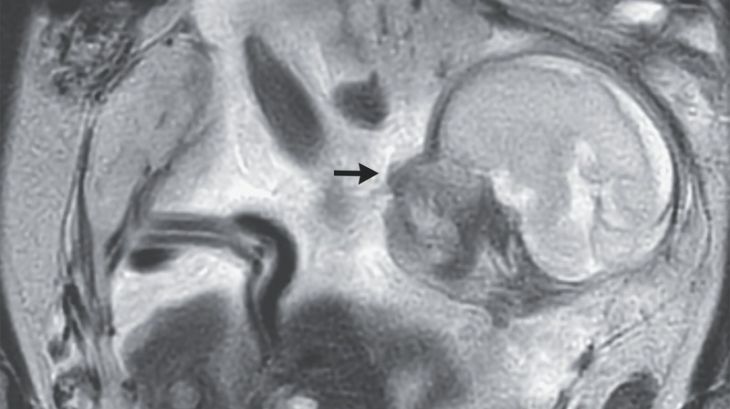

Sin embargo, en el caso de la mujer de Francia, el bebé se alojó en el abdomen y sostuvo su desarrollo en esta zona durante 29 semanas. La madre estuvo acompañada por un equipo de especialistas de la Isla de la Reunión, en Francia, encabezado por Guillaume Gorincour.

El bebé se ancló a la membrana que recubre su membrana abdominal, encima del coxis, y logró un crecimiento normal. Hasta que fue extraído a través de una cirugía.